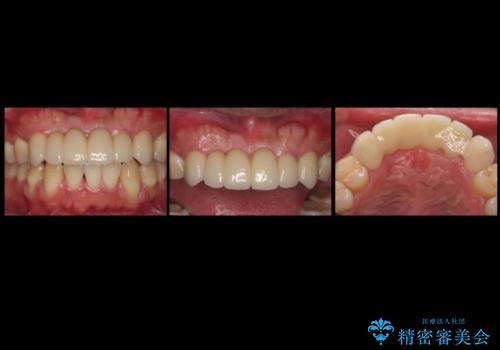

総合歯科治療をやりきったことで、メンテナンスに移行することができました。

また、大臼歯の銀歯もセラミックに全てやりかえています。

左上7番は歯周病によりやむなく抜歯となり、インプラントをおすすめしましたが、希望されませんでした。